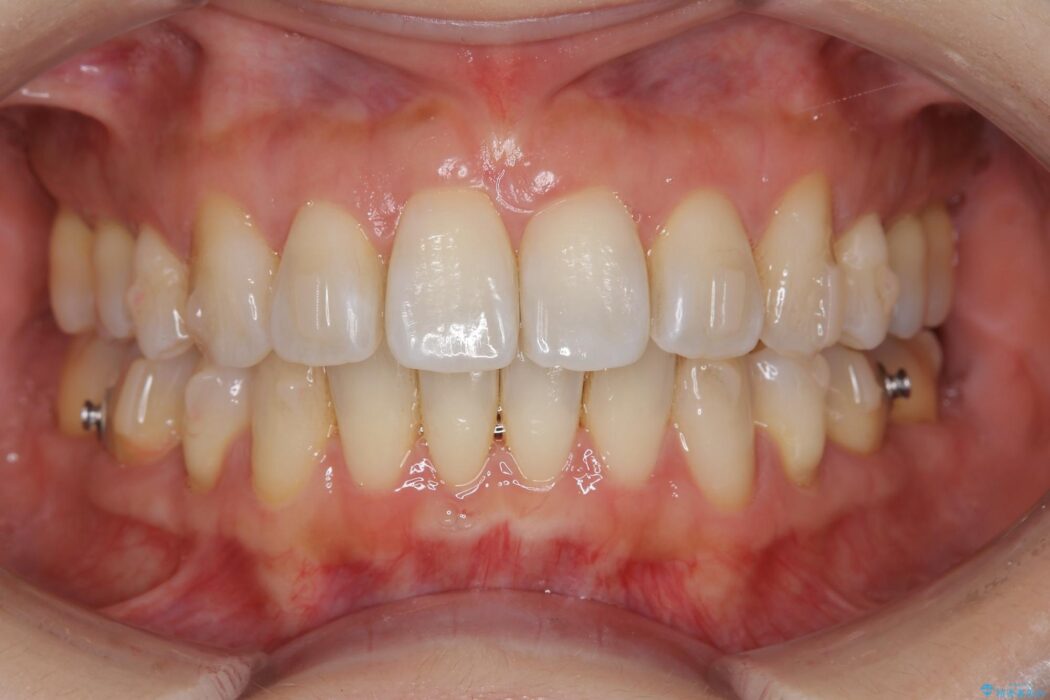

治療後について

歯と歯の間を削るのと、歯列のU字型のアーチを僅かに外側に広げる事でスペースを作り、前歯の角度の改善をしました。

保定装置は、マウスピースと前歯の裏側を細いワイヤーで固定(ボンディングリテーナー)を併用していただいてます。